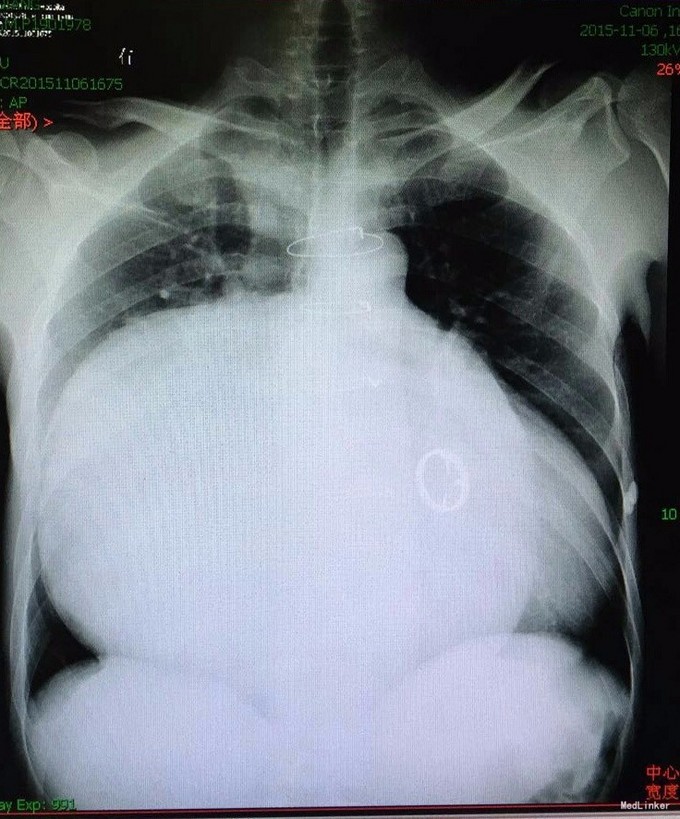

患者男,45岁,因“左髋部摔伤五日余”入院。 患者自诉于五日前步行时不慎摔伤,左髋部着地,伴疼痛,活动受限,遂求治于当地医院,行影像学检查示:左侧股骨颈骨折,给予止痛制动及其他对症支持治疗,治疗后症状无明显好转,遂转入我院,门诊以“左侧股骨颈骨折”收入院。 患者摔伤以来,精神睡眠饮食可,大小便正常,体力一般,体重无明显下降。 既往患者心衰史十余年,新功能三级,口服阿伐他丁、培哚普利、阿司匹林、螺内酯、速尿等控制病情;十年前行瓣膜置换术。其余无特殊。

查体:T:36,2℃,P:86次/分,R:20次/分,BP:135/80mmHg。神志清楚,查体合作,面容正常,全身浅表淋巴结无肿大。心肺腹无异常,双下肢无水肿。生理反射存在,病理反射未引出。 专科情况:患者卧床,不能行走,脊柱生理弯曲存在,未及明显畸形,双上肢皮肤感觉运动可,右下肢皮肤感觉运动可,右髋压痛阴性,右膝压痛阴性,直腿抬高试验90度,四字征阴性,左下肢外旋畸形,较右下肢稍缩短,皮肤感觉可,左髋压痛阳性,左膝压痛阴性,直腿抬高试验及4字征因疼痛不能配合,双侧膝跳反射正常,巴氏征阴性,余生理反射存在,病理反射未引出。 辅检:外院影像学检查是:左股骨颈骨折。我院术前检查无异常,影像学检查见下图。

诊断:左大腿血肿,皮下水肿;心力衰竭(心功能3级) 治疗:止血、脱水、抗心衰、其他对症支持治疗。